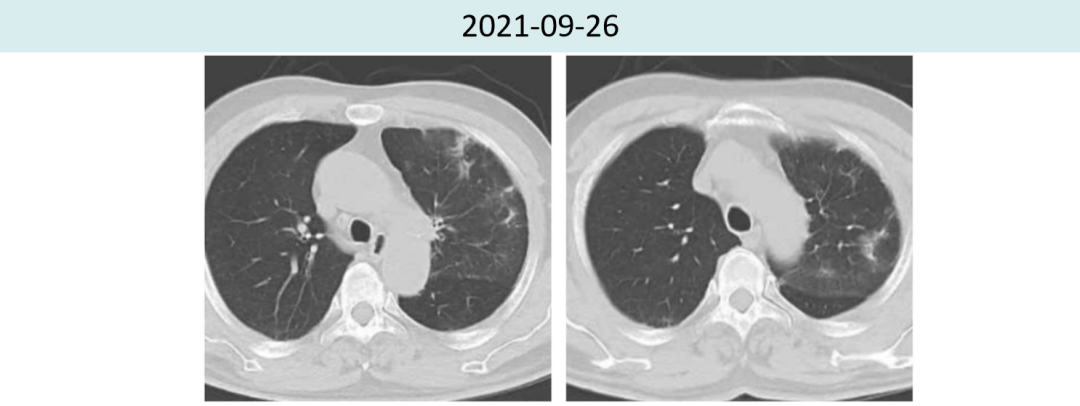

2021年9月26胸部CT提示间质性肺炎较前进?步好转,肿瘤略增大(1.6cm→2.2cm),疗效评价PD。

图2.患者治疗前后肺炎情况对比